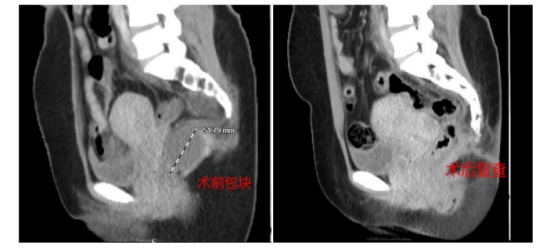

而在3个月前,李女士因胆囊结石伴胆囊炎于当地医院就诊,而腹部CT结果却显示盆腔包块较前并无变化。心急如焚的李女士多方打听,最终在当地医生的推荐下,来到湖南中医药大学第二附属医院普通外科微创中心进一步诊疗。

康复出院后,李女士的脸上每天都堆满了笑容。近期,李女士及丈夫来医院复诊,CT、直肠彩超均未见包块复发。至此,李女士的求医之路终于告一段路。此后,便只需要定期复查就可以了。